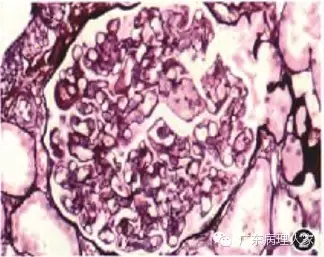

1.肾活检的病理诊断必须密切联系临床,虽然任何病理检查均须与临床表现联系来思考,但对肾活检病理诊断而言,这一点更为重要。因为同一种病理表现可能对应着截然不同的临床肾脏病,由于临床治疗方法不同,一旦误诊,将造成不良后果,如一种以系膜细胞和内皮细胞弥漫增生为特点的肾小球病变,有急性链球菌感染后肾小球肾炎、病毒感染后肾小球肾炎、活动性弥漫增生性狼疮性肾炎(图1)、IgA肾病(图2)、过敏性紫癜性肾炎等多种可能,决定性因素是临床表现和化验指征。另者,同一临床肾脏疾病可有不同的病理表现,仍以临床确诊为系统性红斑狼疮而导致的狼疮性肾炎为例,可分为轻微病变型、轻度系膜增生型、局灶增生型、弥漫球性增生型、弥漫节段增生型、膜增生型、新月体型、膜型、增生硬化和硬化型多种病理类型。所以,从事肾活检病理诊断的病理医师,一定要具备必要的临床肾脏疾病知识。

图2毛细血管内增生性IgA肾病,肾小球内皮细胞和系膜细胞弥漫增生 PASM染色 高倍放大